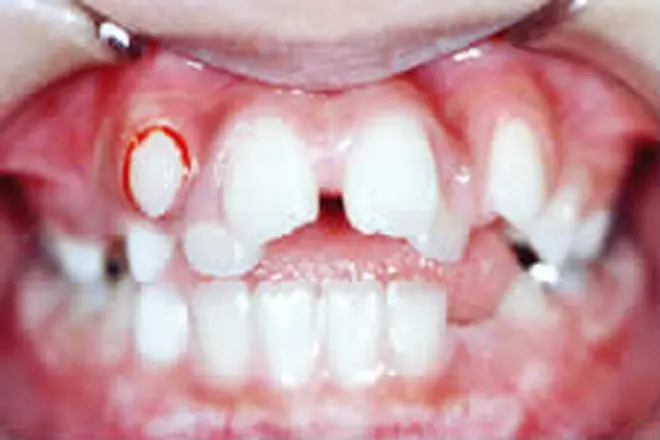

子どもの矯正 治療例3

左上の前歯が歯肉に埋まったケースです。

埋まっていた前歯を外科的に露出させました。

矯正装置を装着し、正しい位置へと移動させます。

前歯が正しい位置に移動してきました(治療中です)。

| 患者さまの年齢・性別 | 8歳・男性 |

|---|---|

| 治療期間 | 8ヵ月 |

| 治療費(税込) | 165,000円 |

| 主訴 | 左上の前歯が出てこない |

| 診断名・主な症状 | 上顎左側中切歯の埋伏 |

| 治療に用いた主な装置 | 表側矯正装置 |

| 治療内容 | 歯肉を切開し、埋もれている歯が見えるようにしました。装置を付けて所定の位置まで引っ張り出して歯並びを整えます。 |

| 抜歯部位 | 非抜歯 |